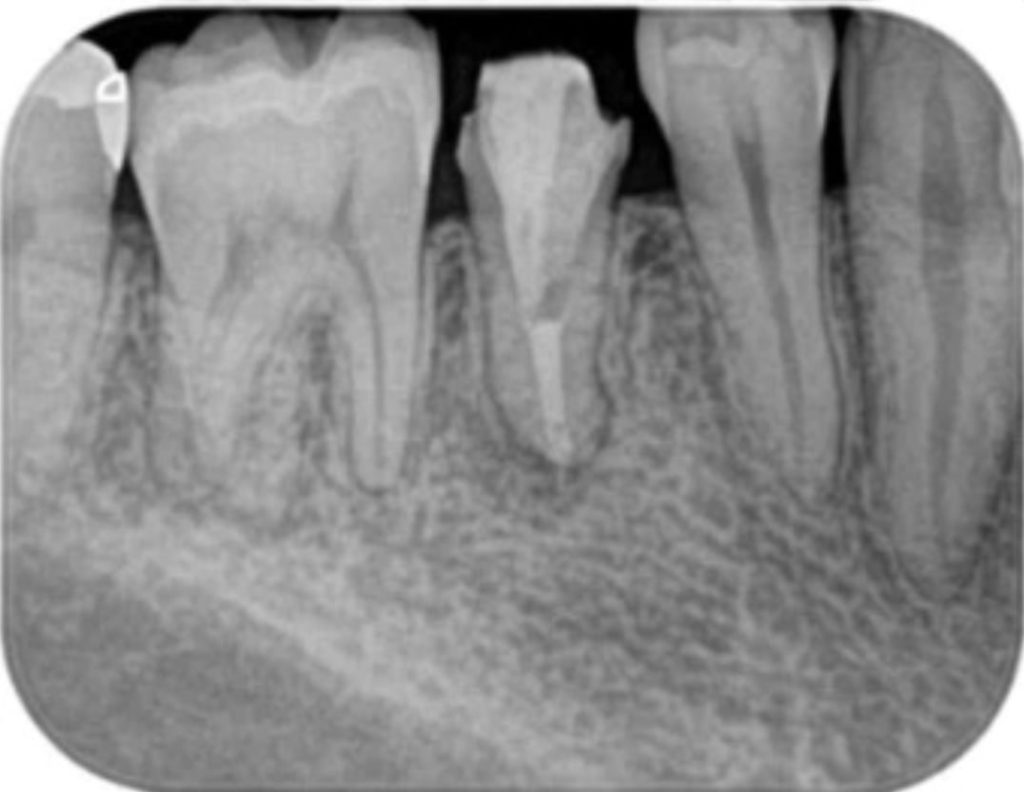

再根管治療(過去に神経の治療をした歯のやり直し)

術前(長い金属の棒を取る+感染を治すために紹介された)

術後(長い金属の棒はマイクロスコープ下で安全に除去し薬を詰めた状態。わずかに画像が変化し治癒してきている)

残念ながら初回の根管治療が上手くいかず再根管治療になると難易度が上がり、成功率は低下します。再根管治療は専門医に紹介すべき症例の1つです。